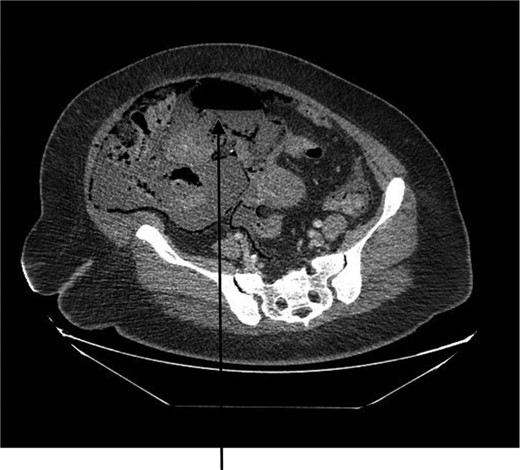

A 44-year-old female presented to the emergency department with generalized abdominal pain that became suddenly severe and diffuse 5 hours before presentation. She described the pain as sharp, alleviated by lying still on her back and worsened by moving. Pain radiated to her back. She also had watery non-bloody diarrhea that started 2 weeks before presentation. She had a medical history of poorly controlled type 1 diabetic mellitus and hypertension. No history of STDs or IUD use. Some of her labs on presentation were as follows: WBC 7.400/mm3, hemoglobin 15.6 g/dl and blood glucose 249 mg/dl. On examination, we found a hypotensive, dehydrated, obese female in septic shock with a tense, massively distended abdomen, which was diffusely tender. CT of the abdomen and the pelvis revealed pneumoperitoneum, a large right abdomino-pelvic mass measuring 17.6 × 12.1 × 20 cm, that appeared to be a septic ovarian cyst (Fig. 1) and diffuse portal venous gas throughout the liver (Fig. 2). Resuscitation and rehydration were initiated, and broad-spectrum intravenous antibiotics were administered. Hemodynamic instability continued, and she was emergently taken to the operating room for an exploratory laparotomy. Upon opening the abdomen pneumoperitoneum and diffuse purulent peritonitis was obvious. There was bullous emphysema of the wall of the uterus. The gallbladder had been previously removed. The stomach, duodenum, small bowel, appendix and colon were normal and involved only by serositis from the purulent peritonitis. A pus-filled right ovarian cyst, subscapular gas bubbles over the liver and a cecal bascule were the dominant abnormalities. A right salpingo-oophorectomy, appendectomy and peritoneal lavage with 15 liters saline and antibiotics were accomplished. She received a total of 7 liters of intravenous crystalloid resuscitation intraoperatively and 2 units of packed red cell transfusion. The patient was transferred to the surgical intensive care unit (SICU) after the procedure to continue resuscitation and critical care therapy for ongoing septic shock. The patient made a complete recovery and was discharged after a total of 11 days in SICU and 23 days in the hospital ward.

CT abdomen showing large air-filled right abdominal mass that appears to be a septic ovarian cyst.